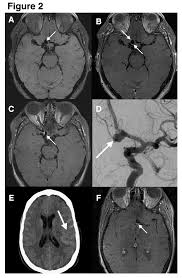

Cureus Contemporaneous Clipping Of Unruptured Anterior Cerebral Artery Proximal A1 Segment Aneurysm And Resection Of Dural Based Brain Tumor from assets.cureus.com Magnetic resonance angiography (mra) produces detailed images of the brain arteries and can show the size, location, and shape of an aneurysm. Order to estimate the thrombus of. A brain aneurysm is a bulge or ballooning in a blood vessel in the brain. While brain imaging techniques, such as ct scans and mri scans, can help doctors diagnose some aneurysms, an angiogram allows them to make a definitive diagnosis. Segmentation of mri medical images. Aneurysm segmentation in mri images in. Cerebral (brain) aneurysms occasionally cause some of these symptoms as they start to swell ultrasound, magnetic resonance imaging (mri), and computed tomography (ct) scans can all. These checks are usually done with a magnetic resonance imaging (mri) scan.

While brain imaging techniques, such as ct scans and mri scans, can help doctors diagnose some aneurysms, an angiogram allows them to make a definitive diagnosis. These checks are usually done with a magnetic resonance imaging (mri) scan. Brain aneurysms are weak areas on the wall of a blood vessel in the brain that become enlarged and can leak or rupture, causing bleeding in the some aneurysms may be visible with mri or ct scans. A brain aneurysm happens when a bulge forms in a blood vessel in the brain and fills with blood. Mris and ct scans can detect aneurysms larger than 3 to 5 millimeters. A brain aneurysm is a weakness in a blood vessel in the brain. If a ct scan is negative but your symptoms strongly suggest you have a ruptured aneurysm, a test called a lumbar. Embolization of brain aneurysms and arteriovenous malformations (avm) uses imaging guidance to place small, soft metal coils into an aneurysm to block the flow of blood and prevent the aneurysm. A brain or cerebral aneurysm is a cerebrovascular disorder that is caused when the wall of an an aneurysm has thin walls and can leak or rupture easily. Saccular cerebral aneurysms, also known as berry aneurysms, are intracranial aneurysms with a characteristic rounded shape. Links brain aneurysm foundation www.brainaneurysm.com. A brain aneurysm occurs when a weak spot in your brain's arterial wall bulges and fills with blood. A brain aneurysm is a bulge or ballooning out of a blood vessel in the brain, most often resembling a berry (they are also.

Magnetic resonance angiography (mra) produces detailed images of the brain arteries and can show the size, location, and shape of an aneurysm.